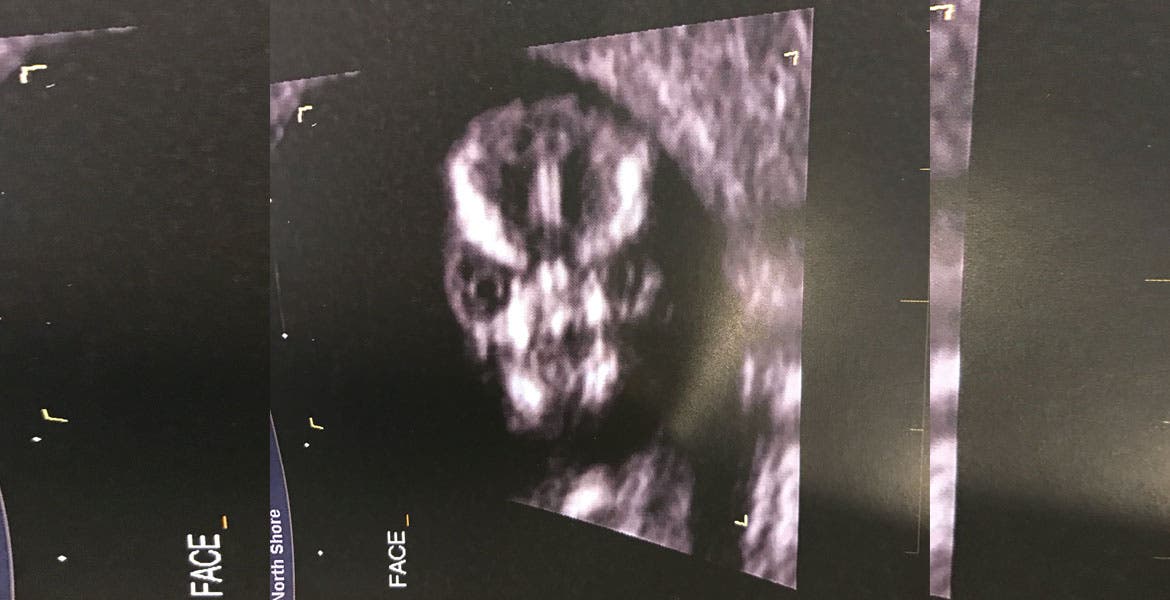

Una mujer australiana compartió por medio de su cuenta de Twitter, la imagen del ultrasonido de su bebé, pero las respuestas de los usuarios no fueron muy agradables.

Sharni Turner escribió en la red social que el técnico que realizó el procedimiento, decidió hacer una toma frontal de la cabeza del feto, lo que resultó ser "lo más aterrador" que ella hubiera visto.

Esta inusual ecografía se ha vuelto viral e incluso muchos especulan sobre la supuesta "criatura" que esta mujer está esperando.

Hasta la futura mamá lo toma con mucho humor.

"No voy a dejar que él [su hijo] la olvide [la ecografía]", "tendré que vestirlo de rosado y hacerlo parecer más lindo", expresó.

Pero para finalizar con las burlas, decidió subir otra imagen del ultrasonido, en la que se ve mucho mejor.